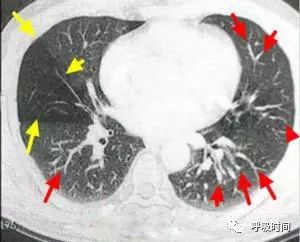

众所周知,肺纹理主要由肺动脉分支组成,故又称为血管纹理。某处亚段以上肺动脉分支发生栓塞时,超急性期即可见到局部肺纹理(肺动脉分支)的缺失区(图 3);局部肺野密度减低。

图 3 胸部正位片:右肺栓塞。片示右中肺野血管纹理减少,密度减低(黄箭头);红箭所示为正常肺纹理。